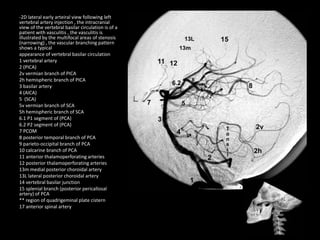

-2D frontal view following left vertebral

artery injection , the intracranial view of

the vertebral basilar circulation is of a

patient with vasculitis , the vasculitis is

illustrated by the multifocal areas of

stenosis (narrowing) , the vascular

branching pattern shows a typical

appearance of vertebral basilar circulation

1 vertebral artery

2 (PICA)

2v vermian branch of PICA

2h hemispheric branch of PICA

3 basilar artery

4 (AICA)

5 (SCA)

5v vermian branch of SCA

5h hemispheric branch of SCA

6.1 P1 segment of (PCA)

6.2 P2 segment of (PCA)

7 PCOM

8 posterior temporal branch of PCA

9 parieto-occipital branch of PCA

10 calcarine branch of PCA

11 anterior thalamoperforating arteries

12 posterior thalamoperforating arteries

13m medial posterior choroidal artery

13L lateral posterior choroidal artery

14 vertebral basilar junction

15 splenial branch (posterior pericallosal

artery) of PCA

** region of quadrigeminal plate cistern

17 anterior spinal artery

-2D lateral early arteiral view following left

vertebral artery injection , the intracranial

view of the vertebral basilar circulation is of a

illustrated by the multifocal areas of stenosis

(narrowing) , the vascular branching pattern

shows a typical